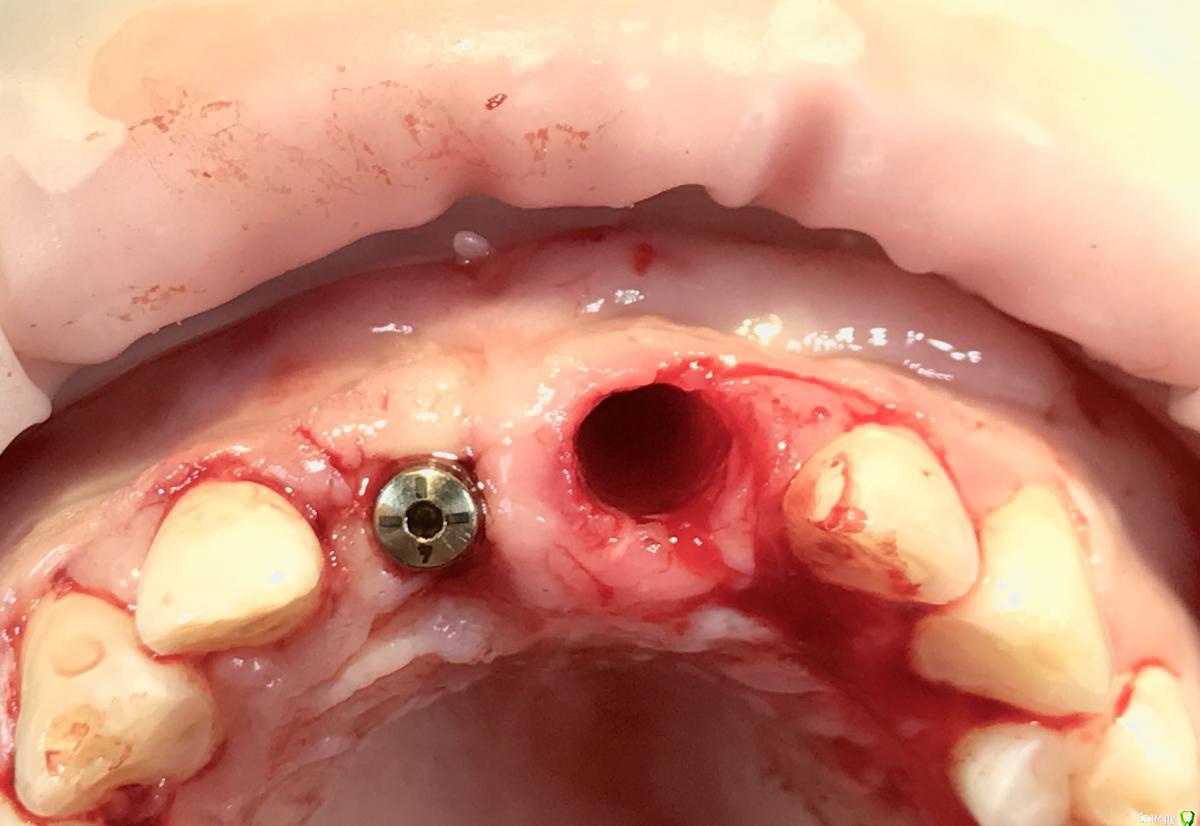

колесников Опубликовано 24 июня, 2018 Поделиться Опубликовано 24 июня, 2018 Совсем забыл,Вы ведь с ev работаете. Поставьте профайл +сст и не ломайте голову. Вот аналогичный случай с похожей анатомией . Компактной пластинки нет,торк 0,апекс импланта ступенькой на улице. 4 Ссылка на комментарий

колесников Опубликовано 22 июня, 2018 Поделиться Опубликовано 22 июня, 2018 Возможно я не прав ,поправьте. Красным выделил то что останетсяЧёрным участки анкилозаЖелтым окончатая перфорацияЗелёным щит.Я делаю так: выделяю щит,остальное удаляю. Кюретаж,ревизия периапикально. В окно плотно колапол и следом немного графт (можно и не выводить графт,так иногда спокойнее). Сложнее всего выбрать диаметр и длинну импланта,хочется нагрузку,но нехочется проблем. Беру в запас на выбор несколько размеров. Можно и визуализировать как вы предлагаете,разрез апикально,но в данном случае не вижу в том смысла. И да,Имплант верхушкой может выходить через окно наружу,в этом нет ничего страшного ни сейчас ни в перспективе. Ссылка на комментарий

Дмитрий Л. Опубликовано 24 июня, 2018 Поделиться Опубликовано 24 июня, 2018 Если кортикальная сохранится и вы в зазор между кортикалкой и имплантатом внесёте биоосс то смысл мембраны? Если графт будет контактировать вестибулярно со слизистой то лучше закрыть. По поводу главного вопроса. А вообще здесь толстый биотип и всё будет хорошо)Кстати вы планируете удалять сосудисто-нервный пучок или просто засверлитесь? И какой абатмент будете использовать? Ссылка на комментарий